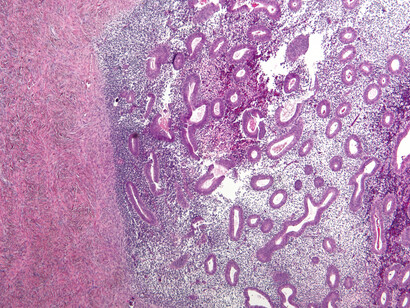

Endometriosis

Si al bajar el período te duele tanto que tienes que parar tu vida unos días cada mes, algo no va bien. ¿A ver si te sientes identificada? Tienes un malestar intenso con dolores punzantes en el abdomen, espalda baja y pelvis, y síntomas como la fatiga, problemas intestinales y cambios en los patrones de menstruación. ¿Sí? Pues eres candidata a sufrir endometriosis.

Es una enfermedad que padecen entre un diez y un quince por ciento de las mujeres. Como ves, es más habitual de lo que parece y le puede pasar a cualquiera de nosotras.

Se produce cuando el revestimiento del útero (el endometrio) es muy rebelde y decide crecer en lugares donde no debería, como en los ovarios, las trompas de Falopio e incluso en otros órganos. Al llegar la regla, estos tejidos "rebeldes" también sangran y causan dolor, inflamación y, en algunos casos, la formación de tejido cicatricial (llamado tejido fibroso o adherencias).

Pruebas para detectar la endometriosis

Es muy probable que tu gine te haga un cuestionario previo. Lógicamente, si la sospecha es alta, te prescribirá pruebas diagnósticas para detectarla. Las más habituales son una ecografía, una biopsia, una resonancia magnética, un análisis de sangre y un examen pélvico. ¡Tranquila, no te va a hacer todas, el "médicx" sabe cuáles son las indicadas para ti!

A lo mejor te asustas si te piden hacer una biopsia de endometrio, pero no te preocupes, es un procedimiento rápido y el dolor es bastante leve, parecido al de la menstruación. A veces, te pueden sugerir tomar un analgésico antes de la prueba.

En cuanto a la ecografía, otra prueba común para detectar la endometriosis puede realizarse a través de la pelvis o la vagina. Es recomendable ir al baño antes para facilitar una mejor visión a través de la ecografía vaginal.

La endometriosis es una afección seria y el diagnóstico temprano es clave para abordarla de manera efectiva. El problema es que, en muchos casos, el dolor menstrual se normaliza tanto que puedes pasar años sin un diagnóstico adecuado y sin saber por qué estás sufriendo tanto.